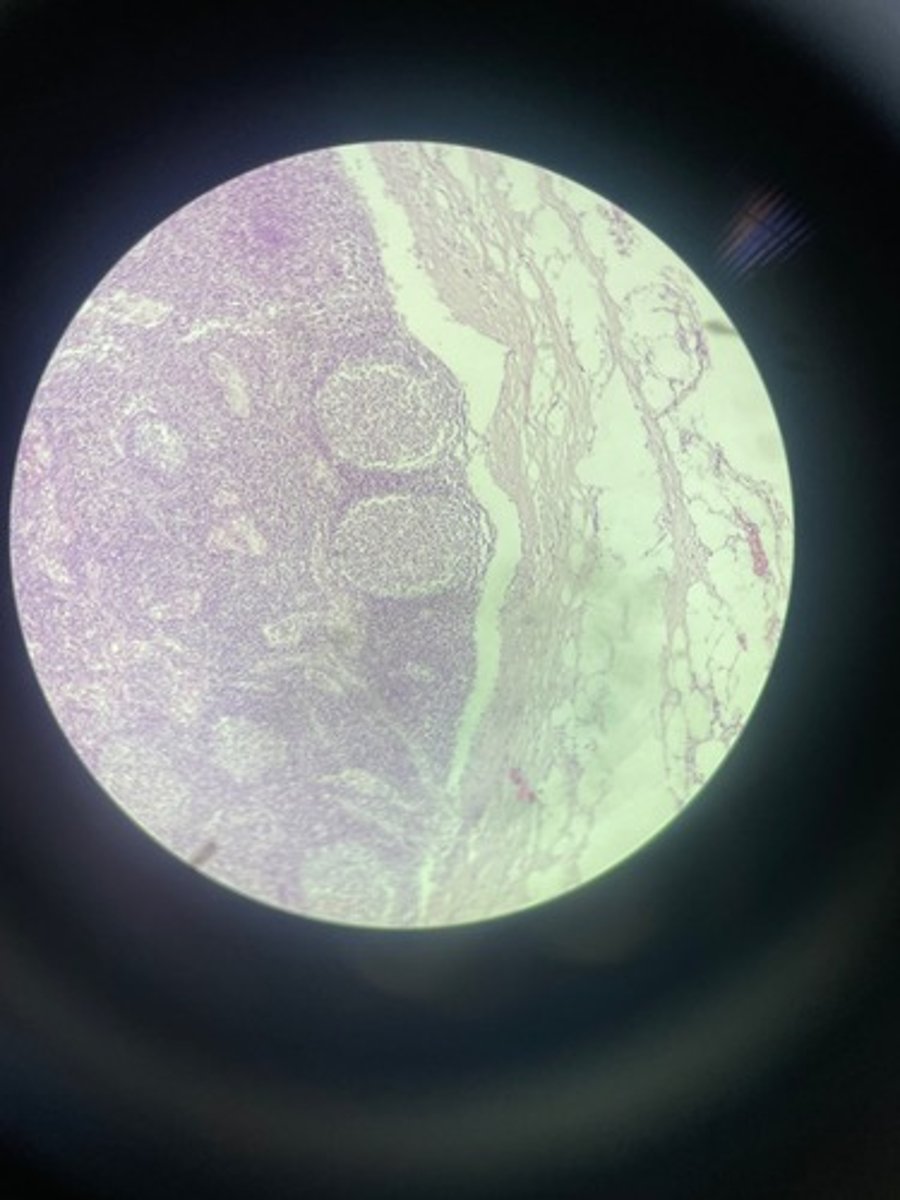

Lymph node HE

Lymph node HE

Lymph node HE

lymph node HE

Lymph node HE

Lymph nodes HE